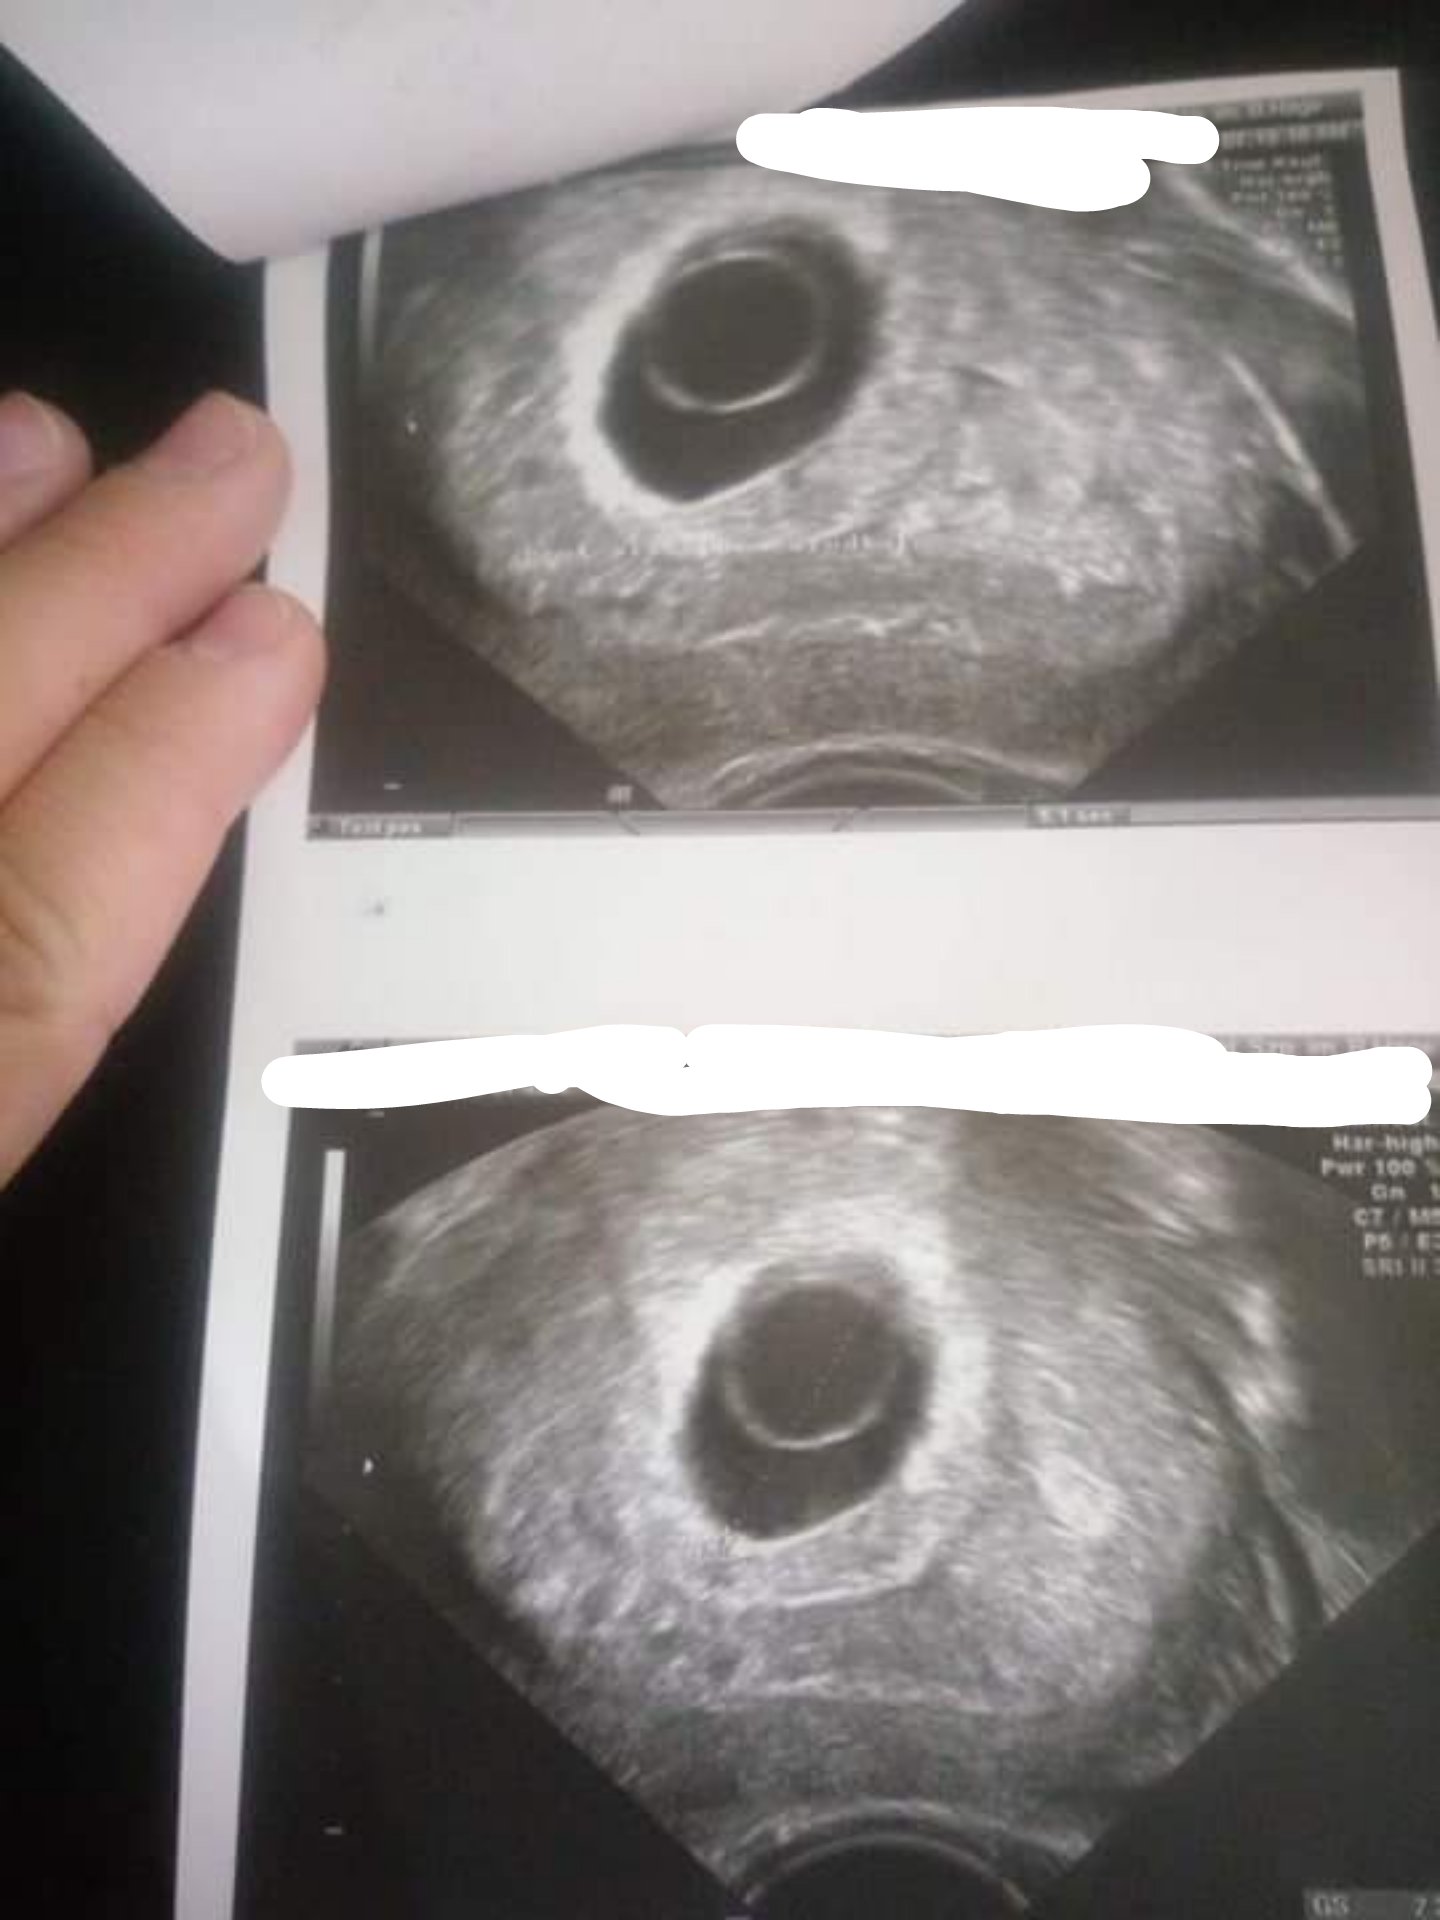

Który masz dzis tydzien przypomnij mi proszę :) Super ze jest cialo zolte, znaczy ze Bedzie zarodek [emoji173]

Chciałabym cos wyjaśnic, bo juz drugi raz to czytam tu na forum.

To, ze jest ciałko zólte nie oznacza, ze na pewno bedzie zarodek. Ja miałam pecherzyk z ciałkiem zółtym, zarodek sie nie pojawił, w szpitalu diagnoza jako puste jajo płodowe.

Ale oczywiscie w tym przypadku ciąża jeszcze młoda i na dniach zarodek pewnie się pojawi [emoji4]